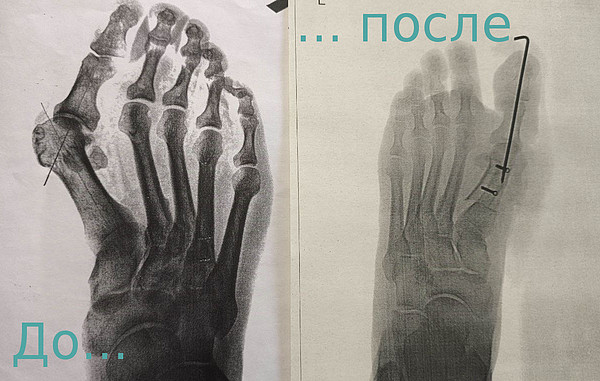

стопы.